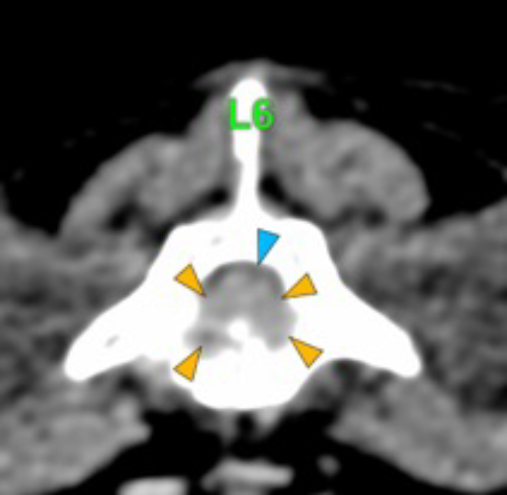

The osteolytic lesions have soft tissue attenuation that shows moderate and slightly heterogeneous post-contrast enhancement. In some of the vertebrae, the lesions cause lysis of the cortex and extend into the vertebral canal (orange arrows) causing variable degree of compression of the spinal cord and cauda equina (blue arrows). At the level of the vertebral bodies of T7, T8, T9 and T12 the lesions extend into the ventral and central aspect of the vertebral canal causing a mild compression of the spinal cord. At the level of T13, L1, L4 and L5 the lesions extend into the ventral and central aspect of the vertebral canal, causing moderate compression of the spinal cord. At the vertebral body of L6 the lesion extends into the ventral and central aspect of the vertebral canal, at the mid-aspect of L6, occupying approx. 90% of the diameter of the vertebral canal causing a severe compression of the cauda equina. At the level of L7, the lesion extends into the ventral and both lateral aspects of the vertebral canal, causing severe compression of the cauda equina.